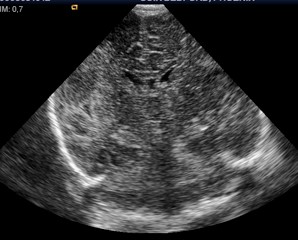

En el estudio de resonancia cerebral a las 48h de vida se aprecia en la secuencia de DWI en el corte axial (imagen de abajo) un infarto arterial de todo el hemisferio cerebral izquierdo, y de todo el territorio de la arteria cerebral media derecha. Se trata de un infarto inmenso bilateral que por ecografía no era tan evidente, de ahí la importancia de solicitar precozmente una RM cerebral con secuencias de difusión que nos permitan un diagnóstico precoz para precisar mejor el pronóstico neurológico y aconsejar a los padres una rehabilitación temprana.